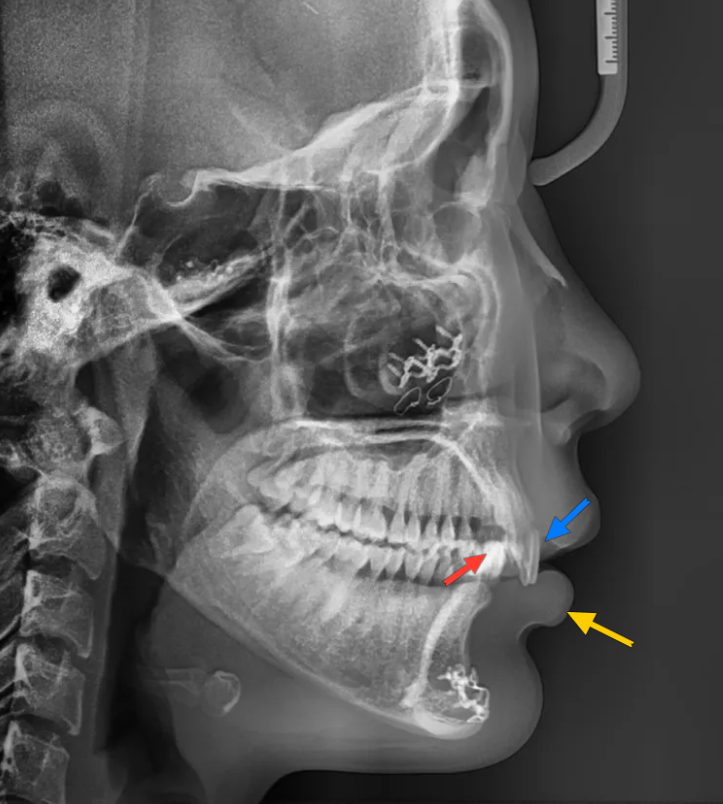

측면에서 보면 오버젯 문제가 조금 더 잘 보입니다

사실 이 환자분은 과거에 아래턱이 작다는 이유로 턱끝수술(턱끝을 앞으로 내미는 수술)을 받으신 적이 있었습니다. 참고로 환자분 같은 경우 윗니가 아랫니보다 훨씬 앞쪽에 위치하게 되므로, 상대적으로 턱이 들어가 보일 수 있습니다.

엑스레이를 보면 윗니(파랑)가 아랫입술(노랑)을 누르고 있습니다.

아랫니(빨강)은 보통 사람과 다르게 윗니의 (중간부분이 아닌) 뿌리와 닿아 있습니다.